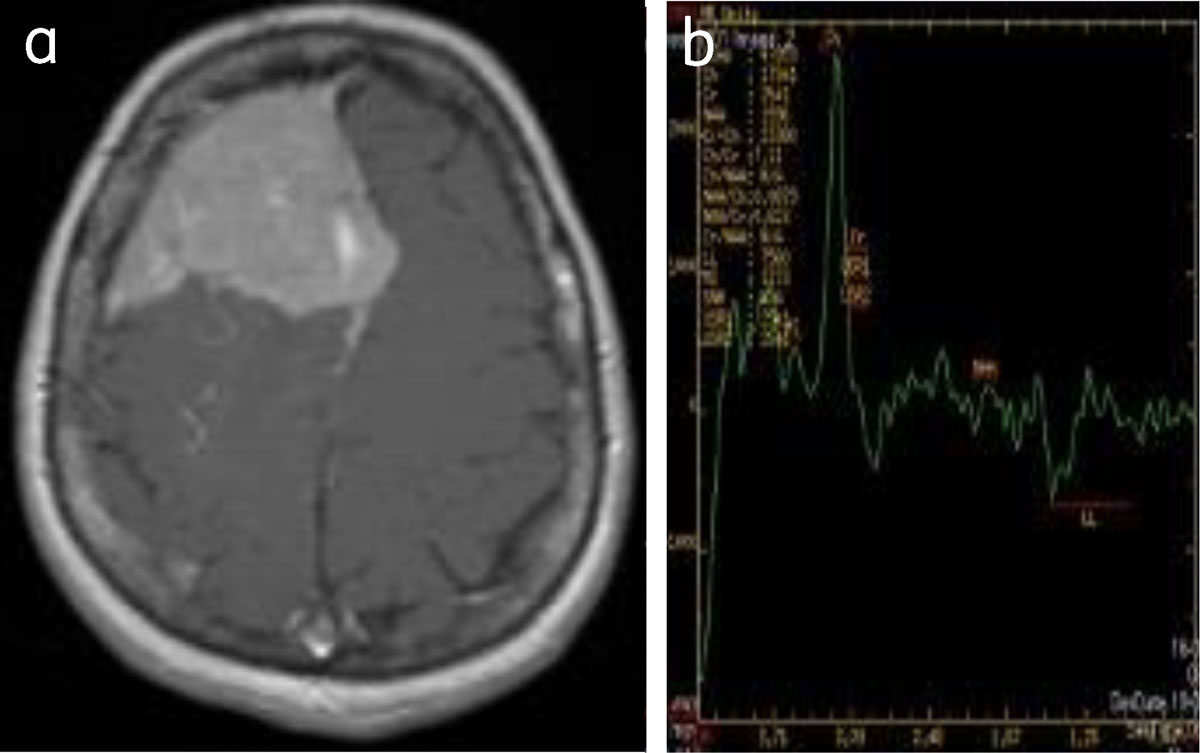

MR spectroscopy shows elevated choline and decreased creatinine in atypical and malignant meningiomas. Alanine is often elevated although glutamate-glutamine and glutathione are more specific [1] (Figure 13).

Figure 13

Convexity meningioma: (a) enhancing right frontal meningioma, (b) MRS shows choline peak with reduced NAA.